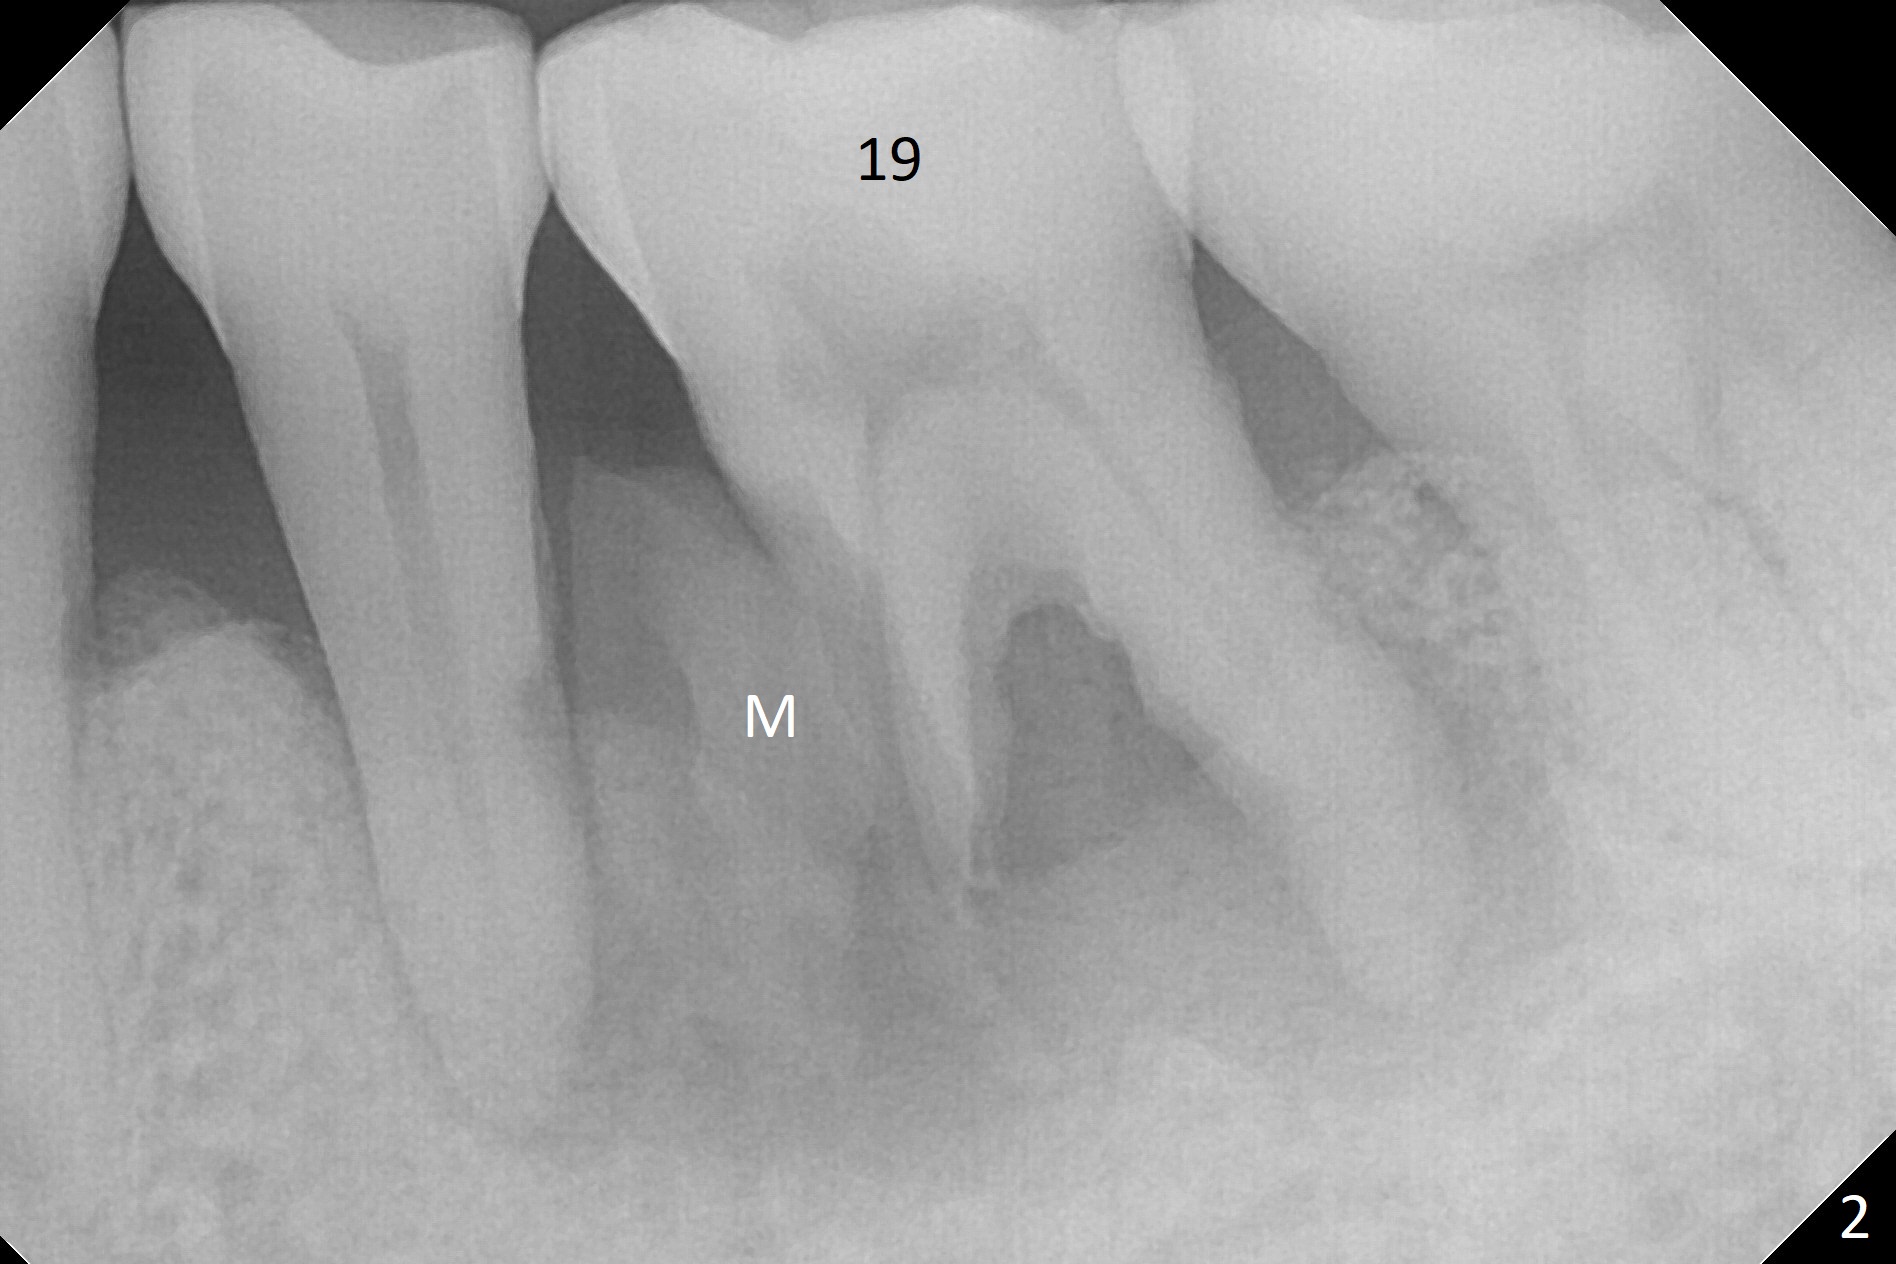

A 63-year-old man is a diabetic with history of good control. He masticates unilaterally with missing teeth #2,3 and 24 (Fig.1 (taken 5 years ago)). The latter has been restored with an implant. Last February the mesial root of the tooth #19 was found to have vertical fracture with bone loss until the base of the septum (Fig.2). The bone available for implantation is ~7-8 mm after root fracture (Fig.3,4). The initial osteotomy depth will be 7 mm (IS kit), followed by the calibrated parallel pin. The latter determines how many millimeters of an implant will be surrounded by the graft bone (Fig.4,5 (green: implant length; pink: cuff; blue: abutment length)). Since the buccal defect is severe with mesial root split (Fig.7 *), draw blood for PRF (2 large tubes). To save the remaining septum, place 2 of 1-piece implants on the either side of the septum (compare Fig.6,8). Take photos to compare buccal vs. lingual gingival recession. Tell the patient that the tooth #20 may be nonsalvageable. Since insurance preauthorization does not get approval for several times, the tooth #19 is extracted with socket preservation and periodontal dressing. The latter dislodges in 1 day. When the patient returns for follow up 4 days postop, the socket is exposed (Fig.9). An immediate implant should have been placed to keep the graft in place. PRF also helps. In fact preauthorization letter arrived 1 day earlier. It appears that guided surgery is indicated for limited bone height. The bone graft appears to gain ~ 5 mm bone in 4 months (Fig.10), which allows to place a 5x8.5 mm implant (Fig.11).